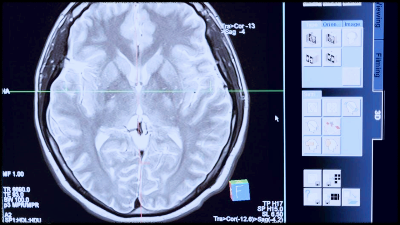

뇌혈관 질환이란?

뇌혈관 질환은 뇌에 혈액을 공급하는 혈관에 영향을 미치는 일련의 의학적 상태를 말한다. 이 상태는 뇌로 가는 혈액과 산소의 흐름을 방해하여 뇌졸중, 일과성 허혈 발작(TIA) 및 혈관성 치매와 같은 합병증을 유발할 수 있다. 특정 생활 습관과 식습관은 뇌혈관 질환의 발병에 기여할 수 있으며, 건강한 습관을 통해 이를 예방하는 데 도움이 될 수 있다.